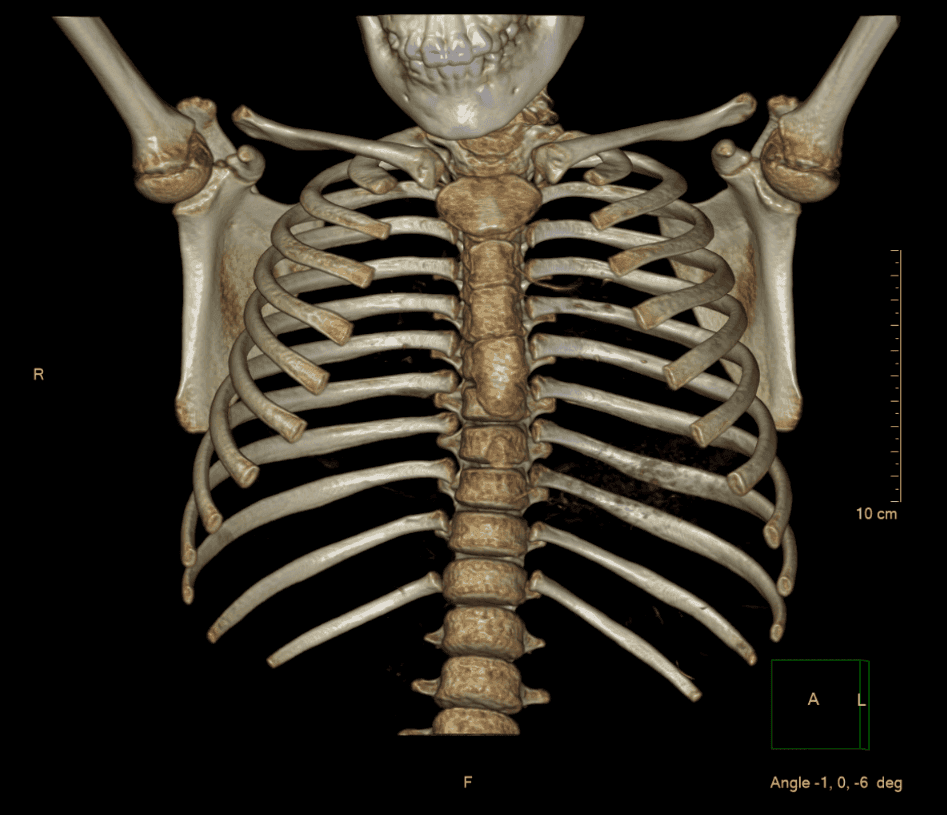

Visualización anatómica volumétrica para planeación quirúrgica.

Nuestra capacidad de realizar reconstrucciones tridimensionales permite a los médicos cirujanos planificar intervenciones con una precisión milimétrica, observando estructuras óseas y vasculares desde cualquier ángulo.